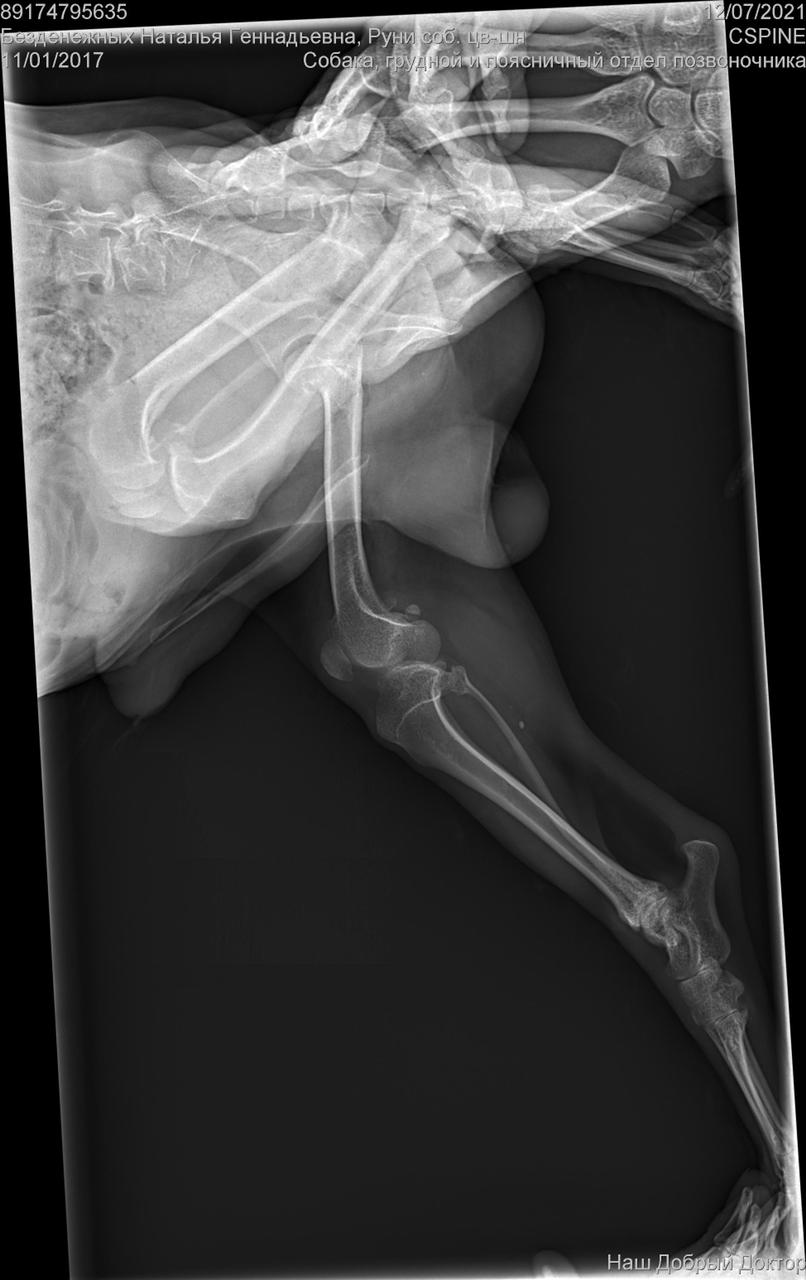

Сегодня утром под окнами дома, по адресу Дмитриева 1, был найден такой замечательный парень, задние лапы похоже перебиты, оставить умирать его я не смогла. Кто-то безжалостно выбросил маленького на улицу и оставил умирать, без еды и питья. Забрала временно к себе, сегодня повезем к ветеринару, оставить у себя возможности нет(моя собака в стрессе) , может кто то его ищет или хочет взять себе, давайте найдём пёсику дом (мама и папу)

С собакой сегодня поедут в клинику. Передержать и полечить смогут. Попросила в клинике посмотреть клеймо и посканировать ип.

ПОнадобится наша помощь с оплатой лечения и поиском дома.